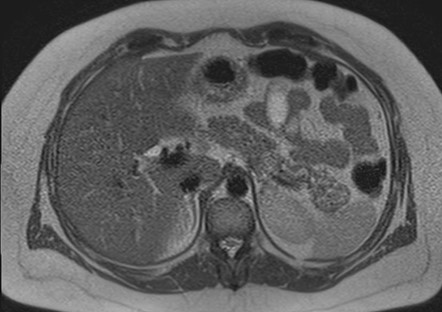

Mujer de 36 años que ingresa a Hospital Sanatorio Franchin el 11 de octubre de 2023 de forma programada para realización de duodeno pancreatectomía cefálica por tumor de cabeza de páncreas en estudio. Refiere hallazgo de lesión en forma incidental durante estudio de control hace dos meses por presentar antecedentes familiares (neoplasia endocrina múltiple). Se interna para manejo quirúrgico. Estudios de tomografía revelan formación nodular localizada en cabeza y cuerpo pancreático de paredes gruesas que mide 24 x 28 mm, que en resonancia se muestra hiperintensa en T2 y realce periférico luego de la administración de contraste endovenoso. Presenta restricción en la difusión con caída de la señal ADC, por lo que se vincula con una lesión de alta celularidad.

Tomografía de abdomen y pelvis con cte ev: del 13/10/2023.

Complicaciones posquirúrgicas

Tomografía de abdomen con cte ev: del 20/10/2023.

Tomografía de abdomen con cte ev: del 26/10/2023.